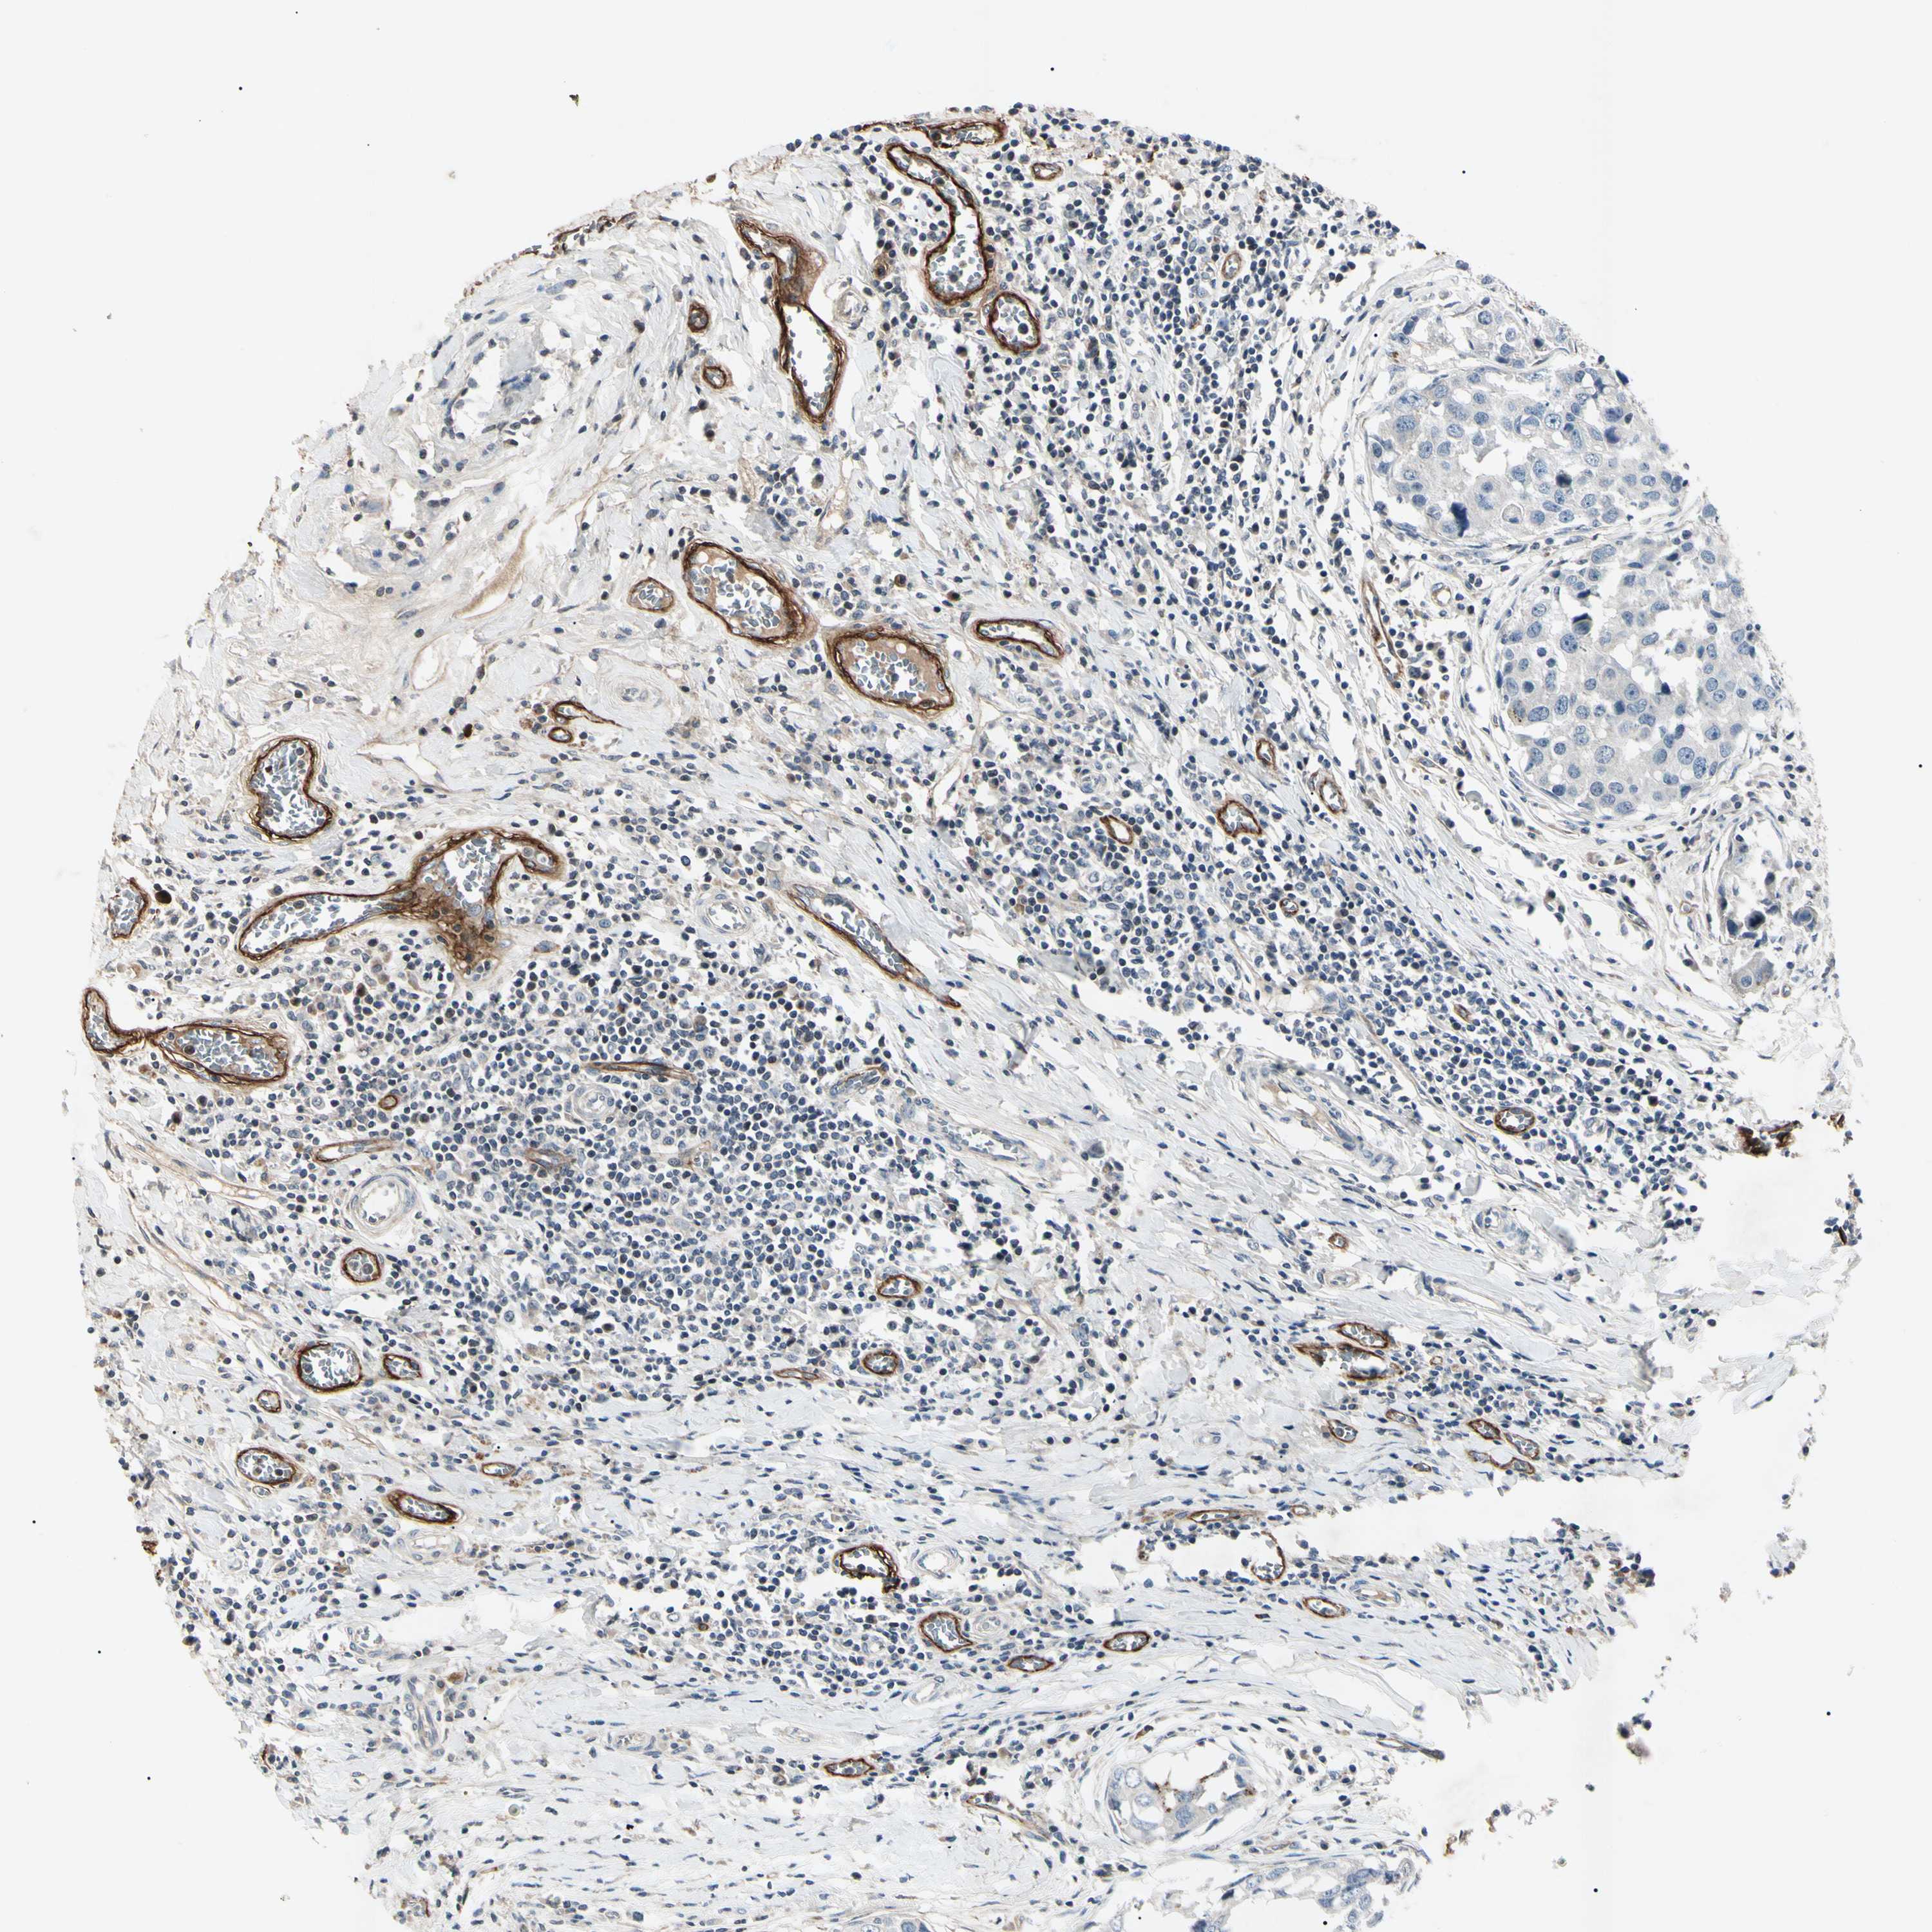

BRCA TCGA BRCA VALIDATION PROTEIN EXPRESSION